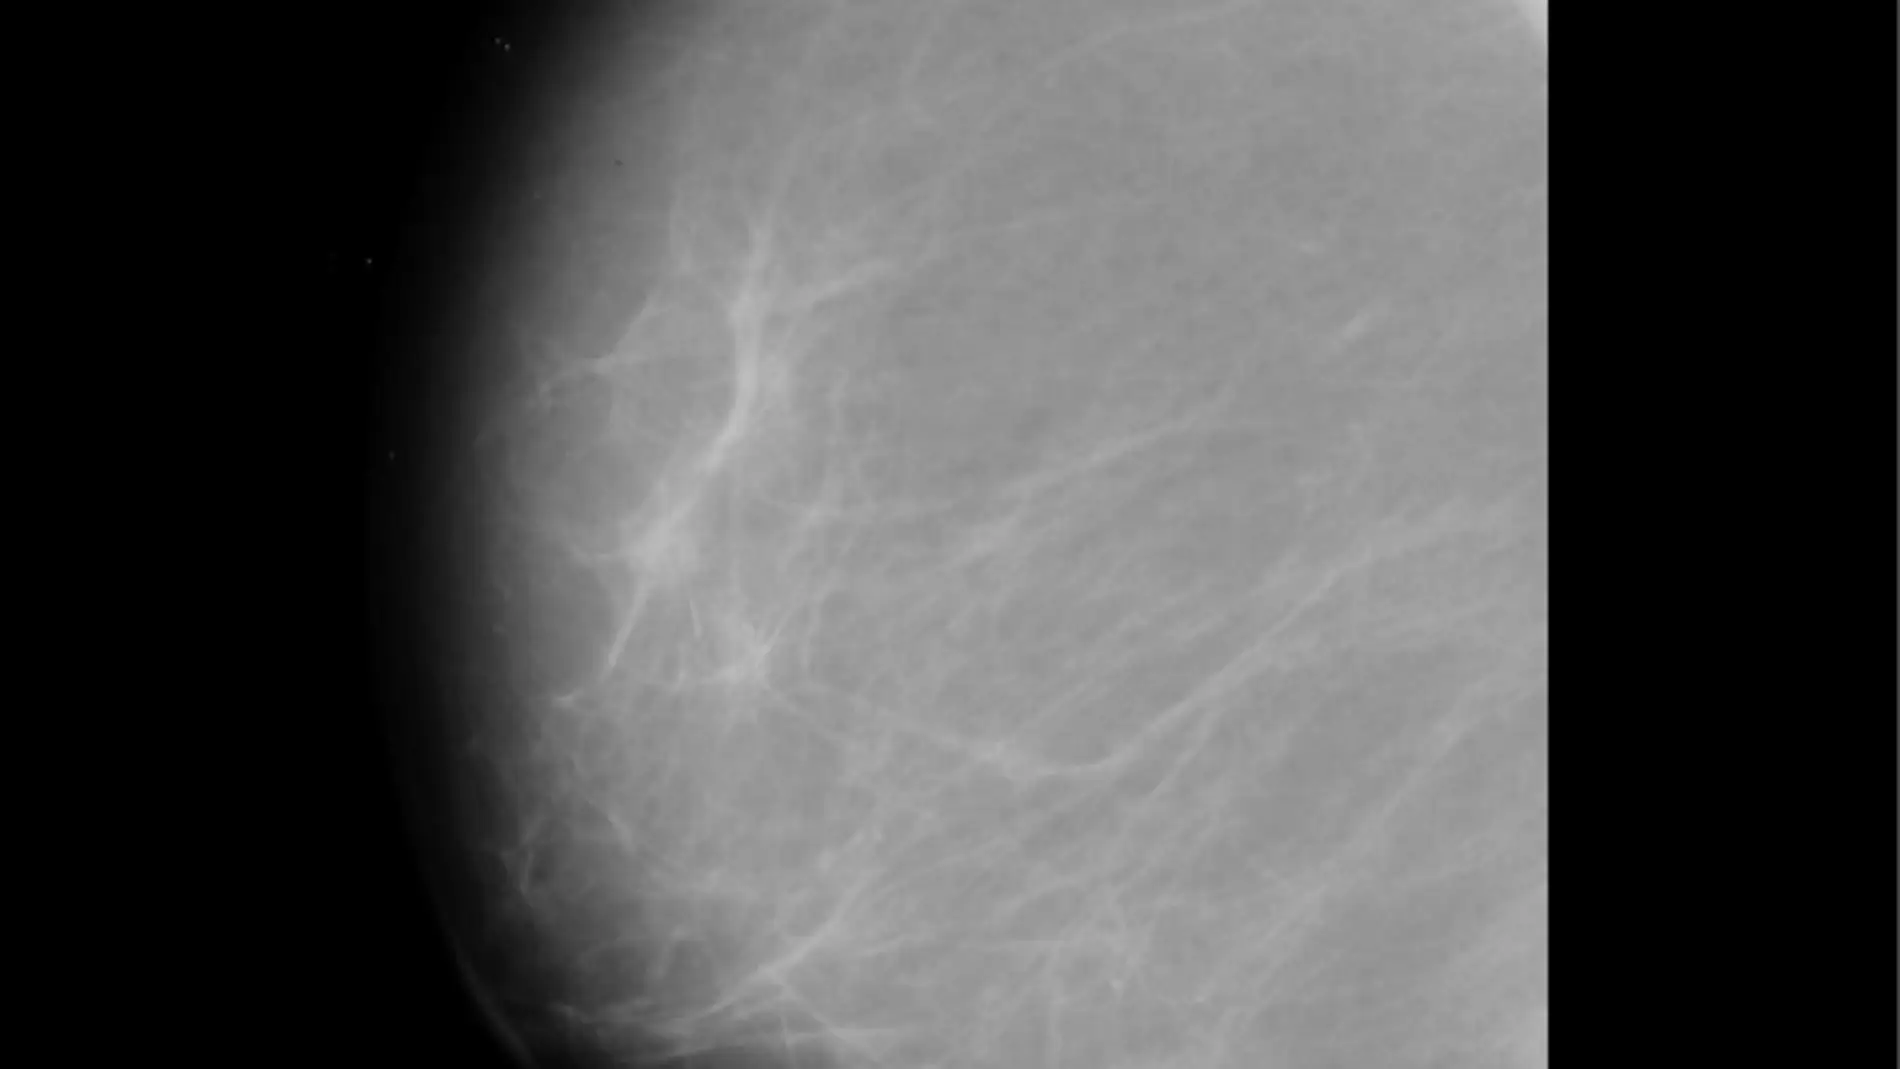

Investigadores de la Universidad Rovira i Virgili en Tarragona han creado un programa que permitirá reducir el número de falsos positivos cuando se detectan tumores a partir de las mamografías. El avance, que alcanza una fiabilidad del 99%, se ha logrado por la combinación de diferentes métodos de análisis de textura mediante visión por computador, con la que se analiza este tipo de pruebas radiológicas.

La mamografía está considerada como la prueba más eficaz para la detección precoz del cáncer de mama, que en 2014 fue la principal causa de muerte por esta enfermedad entre las mujeres de la Unión Europea. Para analizar e interpretar los datos de esta prueba radiológica se utilizan de forma creciente sistemas de diagnosis asistida por ordenador (CAD). Estos métodos no son del todo fiables, ya que en ocasiones generan falsos positivos -la presencia de un tumor que finalmente, en pruebas posteriores, se demuestra que no existe.

Ahora, el estudio de la URV se ha centrado en investigar el efecto de cinco métodos de análisis de textura de las imágenes a las que se han aplicado diferentes técnicas (análisis de resolución de píxeles, escala de integración, algoritmos de preprocesamiento de la imagen y normalización de datos). A partir de aquí se han hecho varias combinaciones hasta encontrar la más idónea para obtener una clasificación mejor de las regiones relevantes –la presencia de tumores o no– dentro de las mamografías.

Con la configuración final obtenida por los investigadores se ha conseguido un 99% de fiabilidad a la hora de determinar la presencia de un tumor en la mama a partir de una mamografía. Este dato mejora los resultados obtenidos con estudios anteriores, cifrados en un 93%, que también habían evaluado la fiabilidad en la interpretación de estas pruebas, pero habían centrado el análisis en otras configuraciones.